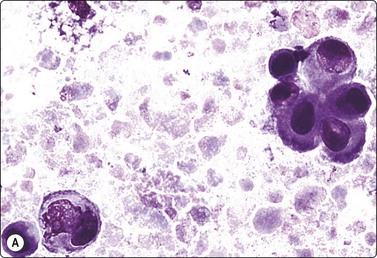

Fig. 7.1 Radiation-induced atypia

(A) The epithelial cells in this irregular cluster show considerable nuclear enlargement, pleomorphism and hyperchromasia, but also some degenerative changes such as loss of nuclear structure (MGG, HP); (B) Corresponding tissue section (H&E, IP).